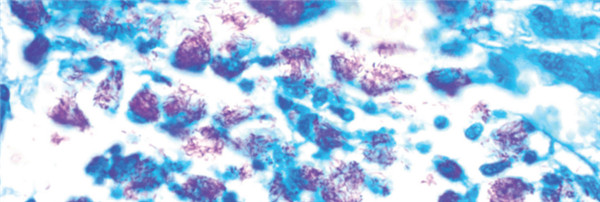

1.Cat# FLS-1,Fite’s Stain Kit (Leprosy & Nocardia Procedures)

組份:二甲苯-花生油溶液;Carbol品紅溶液;酸性酒精1%亞甲藍(lán)溶液

目的: Fite的染色工具包(用于麻風(fēng)病)旨在用于麻風(fēng)分枝桿菌(麻風(fēng)病)的組織學(xué)可視化。 麻風(fēng)桿菌和諾卡氏菌會(huì)染成紅色,而背景會(huì)染成藍(lán)色。該試劑盒里每個(gè)組份也都可以批量購買。

結(jié)果圖: